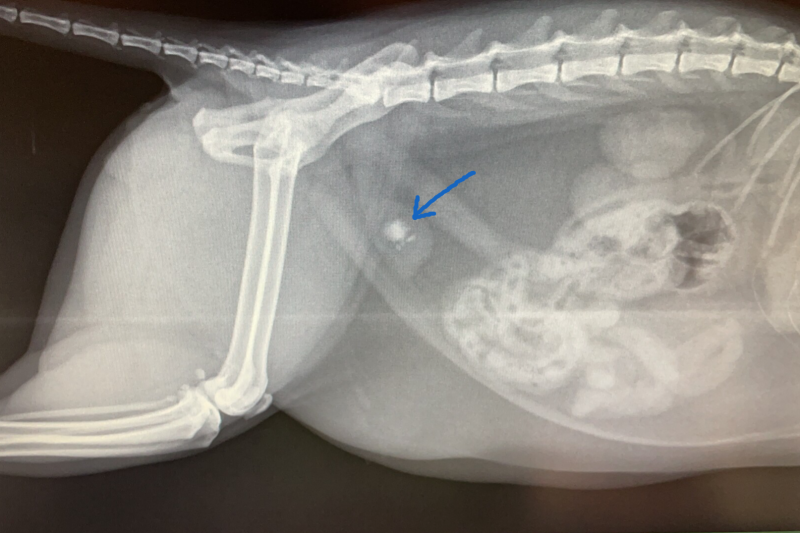

Feline Lower Urinary Tract Disease (aka FLUTD) treft katten wereldwijd en heeft vaak geen aanwijsbare achterliggende oorzaak. Blaasgruis en blaasstenen zijn hier een onderdeel van. Blaasgruis is een opstapeling van mineralen in de urine van de kat die zich tot kleine kristallen omgevormd hebben. Wanneer deze kleine kristallen gaan samenklonteren ontstaan de gekende "blaasstenen" (zie foto).

Deze kristallen en/of stenen irriteren de binnenkant van de blaas en kunnen zo een blaasontsteking in de hand werken. Indien een klein steentje loskomt zal deze in de urinebuis terecht komen en de hele boel blokkeren. We spreken dan van een urinewegobstructie. Dit doet ontzettend veel pijn en is een levensbedreigende situatie!

De diagnose zullen wij stellen adhv uw anamnese, ons algemeen onderzoek, een urineonderzoek, een röntgenfoto en/of een echo.